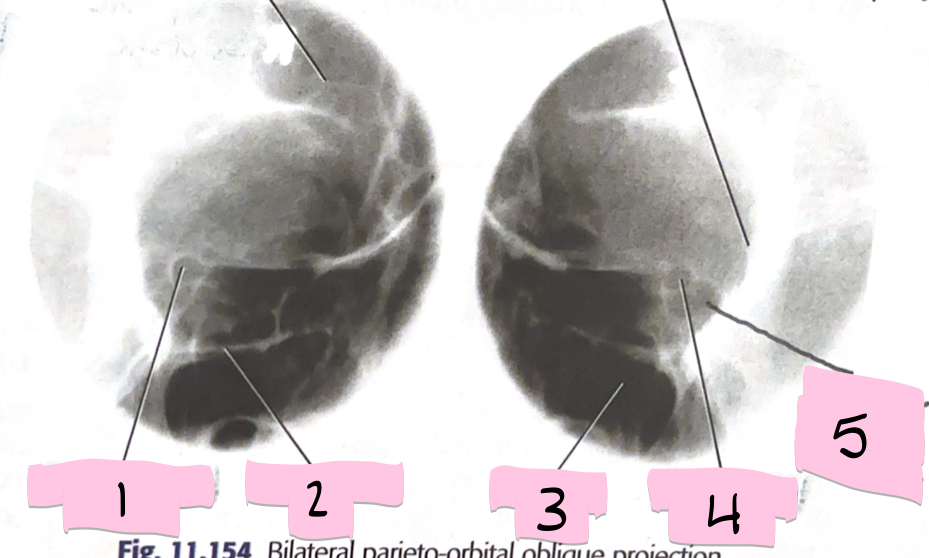

What is 1 pointing to?

Optical foramen and canal

What is 2 pointing to?

Inferior orbital rim

What is 3 pointing to?

Maxillary sinus

What is 4 pointing to?

Optic foramen and canal

What is 5 pointing to?

Superior orbital fissure